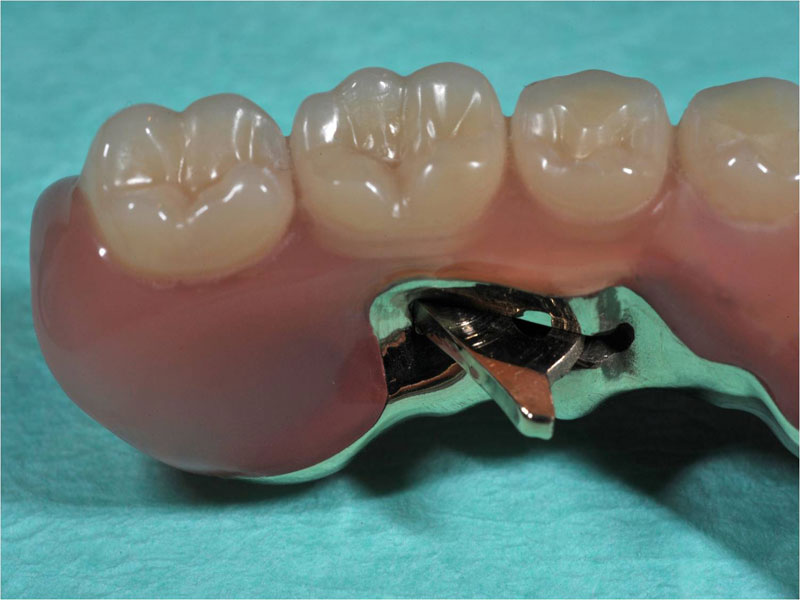

| Hier bieten vier Implantate eine relativ einfache Möglichkeit eine Prothese mit zwei Riegeln optimal zu befestigen. Diese sind an der Prothese im geöffneten Zustand deutlich zu sehen, geschlossen bleiben sie selbst im Spiegelbild des Mundinnenraumes unsichtbar. Sie vergessen alle Druckstellen und Ängste und freuen sich endlich wieder einmal richtig abbeissen zu können! |